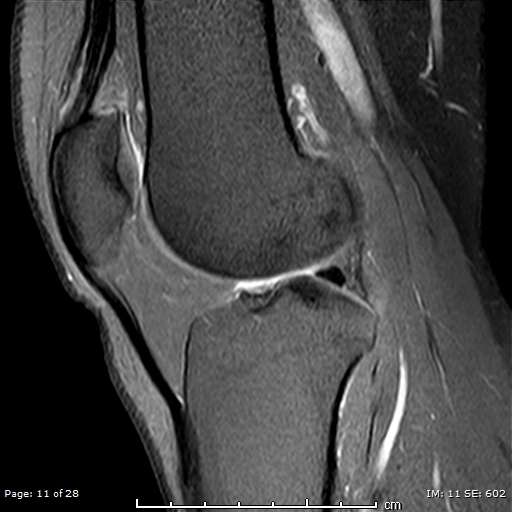

Hội chứng chèn ép túi mỡ trên bánh chè (Anterior suprapatellar fat pad impingement syndrome)